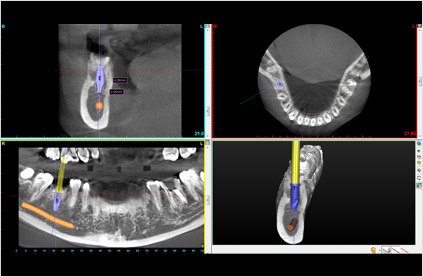

当院で導入しているインプラント術前シミュレーションソフト「SimPlant(シムプラント)」は、最適な埋入インプラントのサイズや植立する方向、位置を決定するために用いられます。術前に何度もシミュレーションできるため、患者様にもご納得いただける治療プランの構築が可能です。3D画像ですから、よりリアルに顎骨の状態(骨密度)を把握することができます。またシミュレーションを行うことで、精度の高いオペをスピーディに行うことができます。「SimPlant(シムプラント)」は数多いインプラント術前シミュレーションソフトの中でも、信頼性が高く、世界中の歯科医院で使われています。